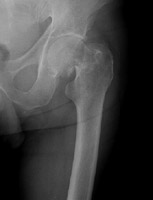

- Click on the image for a larger versionBAP radiograph of the left hip. There is a subtle band of sclerosis at the femoral neck.

- Click on the image for a larger versionCCoronal MRI. This STIR sequence image shows intense signal in the left femoral neck region, due to fracture much more extensive than that predicted by the radiograph. This was a Garden II fracture.